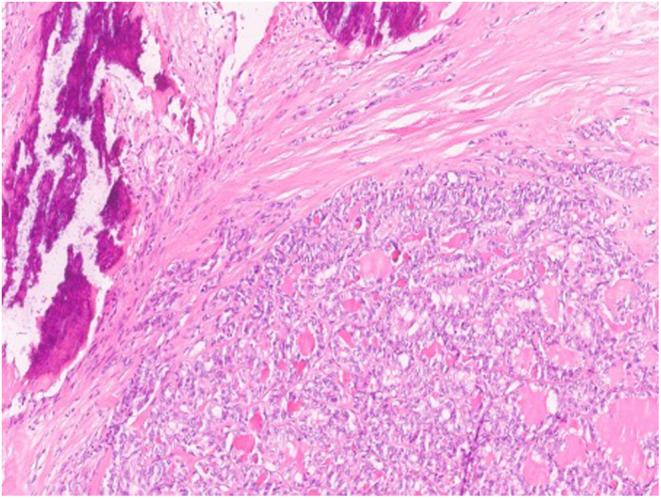

Papillary thyroid carcinoma (PTC) primarily located in the pyramidal lobe of the thyroid gland is extremely rare, therefore the clinical and pathological features are not well understood. The authors describe a case of PTC of the pyramidal lobe, in a 77-year-old woman who underwent en bloc total thyroidectomy with pyramidal lobe, hyoid bone and cervical lymph node excision. In line with the present case, current literature reports a greater presence of worse prognostic factors, namely extrathyroidal extension, advanced T stage or presence of cervical lymph node metastasis. Recently, a new classification has been suggested-Upper Neck Papillary Thyroid Cancer (UPTC)-which encompasses these carcinomas, Delphi ganglion metastases and thyroglossal duct cyst carcinomas, with potential clinical and therapeutic implications, particularly the need for orthotopic thyroidectomy. Also, the complete excision of the pyramidal lobe during thyroidectomy may influence the success of radioactive iodine therapy and the patient's follow-up surveillance.

主要位于甲状腺锥状叶的乳头状甲状腺癌(PTC)极为罕见,因此其临床和病理特征尚不明确。作者描述了一例77岁女性的甲状腺锥状叶PTC病例,该患者接受了包括锥状叶、舌骨和颈部淋巴结切除的整块全甲状腺切除术。与本病例一致,当前文献报道预后较差的因素更多见,即甲状腺外侵犯、晚期T分期或存在颈部淋巴结转移。最近,有人提出了一种新的分类——上颈部乳头状甲状腺癌(UPTC),它涵盖了这些癌、德尔菲神经节转移瘤和甲状舌管囊肿癌,具有潜在的临床和治疗意义,特别是原位甲状腺切除术的必要性。此外,甲状腺切除术中完整切除锥状叶可能会影响放射性碘治疗的成功率和患者的随访监测。